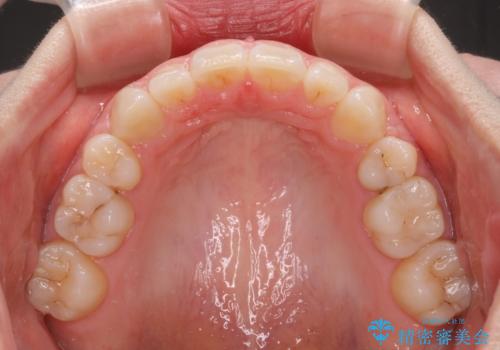

4本の歯を抜歯したことで、飛び出していた口元が引っ込み、横顔が大きく改善されました。

- 矯正装置

- クリアブラケット